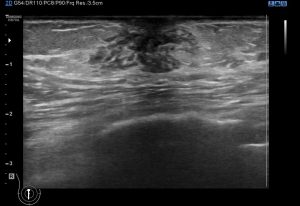

Los hallazgos variables, desde normalidad como la imagen 2 donde ves el botón mamario y nada más, a aumentos de densidad y de tejido, imagen 3, normalmente palpables, en relación con ginecomastia, o ya en niveles superiores, tumores, como la imagen 7, en el tejido mamario.

Vamos a comprobar normalidad, básico, vamos después a detallar hallazgos compatibles con ginecomastia, como aumentos del tejido retroareolar de aspecto hipoecogénico, heterogéneo. en forma de raíz de árbol, unilateral o bilateral y en este caso, no simétrico de forma habitual. Medimos, comprobamos ambos planos, y colocamos doppler para ver.